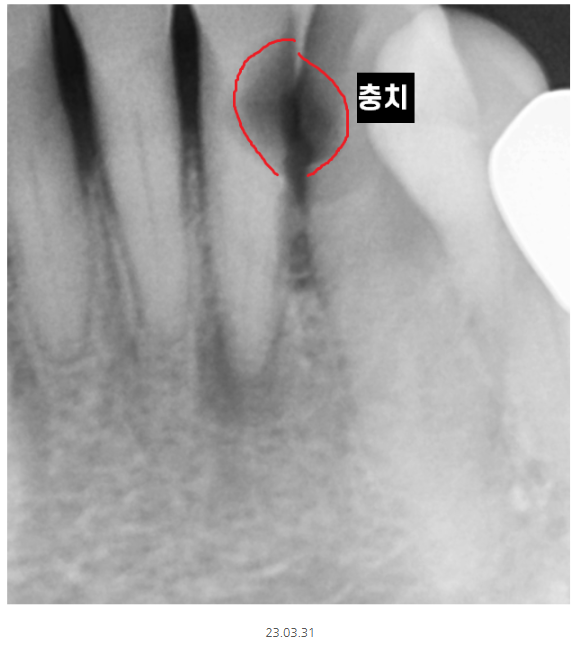

파노라마에서 1차 판별해 보니

의심되는 부분이 있다!!

그러면 추가 검사가 들어가게 됩니다.

이럴 때 선택적으로 작은 x-ray를 촬영합니다.

부분적으로 확대하여 촬영하기 때문에

더 자세히 볼 수 있습니다.

정상적인 치아는 하얗게 속이 보이지만

충치가 파먹은 부분은

까맣게 나타나거든요~

텅~ 속이 비어있기 때문이죠.